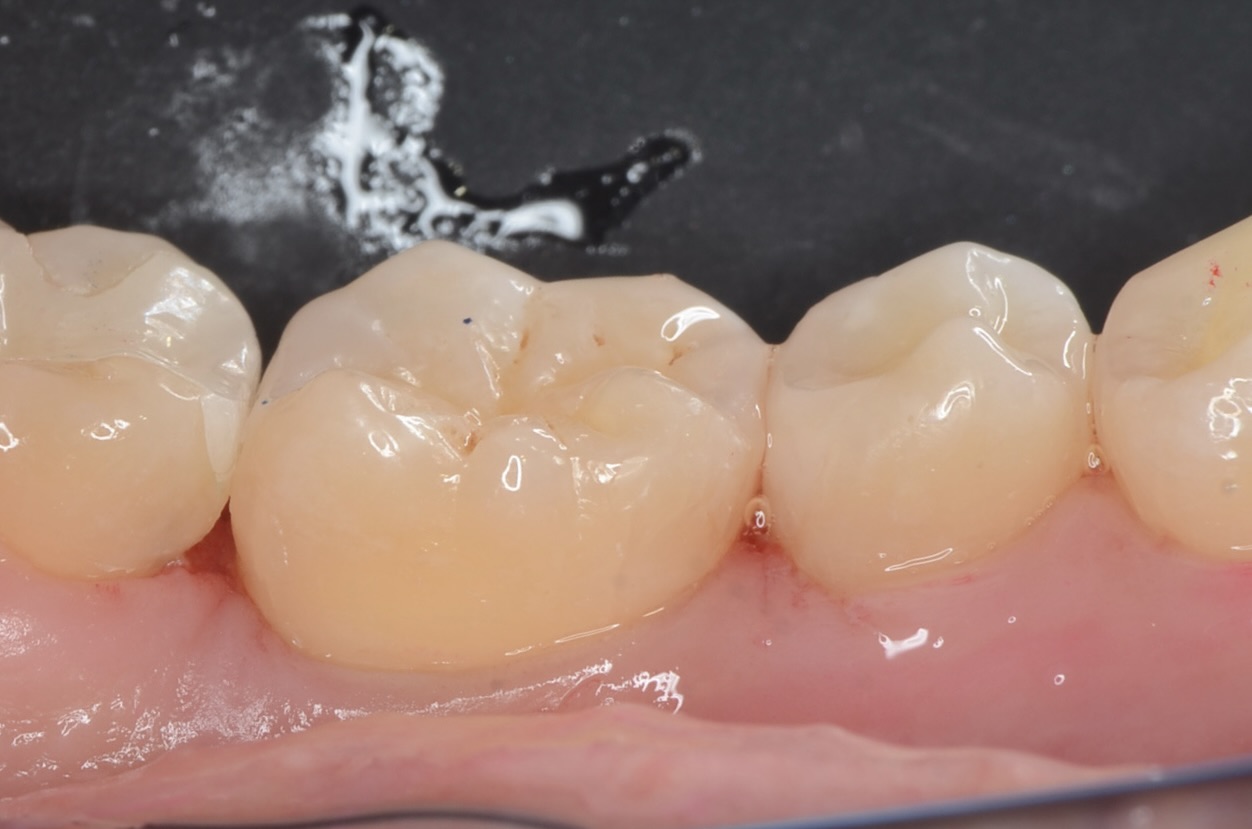

ダイレクトボンディング

天然歯の自然な形態を模倣してレジンを充填しました。 -

後日、形態修正

研磨をしっかり丁寧にすることで、レジンと歯質の段差を修正し、虫歯になりにくくします。 -

硎磨

自然な見た目に仕上がりました。噛み合わせも問題ありません。本当の審美歯科とは、見た目の美しさ・機能・清掃性が伴って成立します。 -

舌側面観

ダイレクトボンディングを検討されている方は、こちらのページをご覧ください。